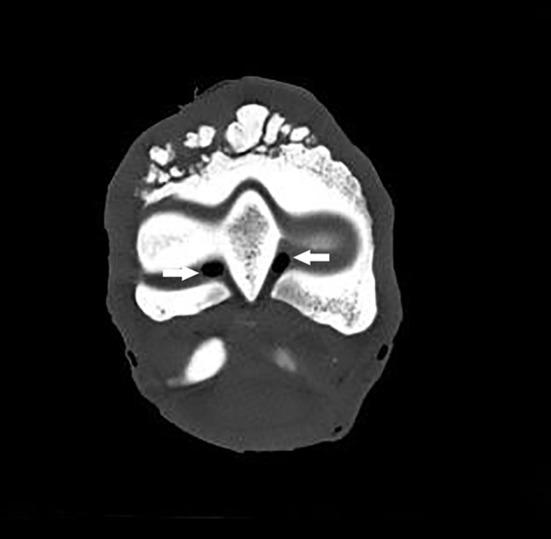

This study aimed at describing anatomo-histopathological and imaging features, using computed tomography and magnetic resonance imaging on six forelimbs of Tbourida horses, that presented a particular bone exostosis on the dorsal and proximal part of the first phalanx, diagnosed by X-ray. Gross anatomy of the bone exostosis revealed an irregular surface with poly-lobulated tissue masses showing a cauliflower shape. The diameter/depth varied from 0.5 to 5.1 cm with a mean of 3.9 ± 0.9 cm. The capsule of the metacarpophalangeal joint was hypertrophic and showed many invaginations in the inner part, in contact with the bone exostosis. Computed tomography revealed cortical and medullary continuity of the bone exostosis, with the underlying bone, and remodeling of the cortical surface of the dorsal and proximal part of the first phalanx. Magnetic resonance imaging showed an increased signal intensity of the bone exostosis on the T1- and T2-weighted gradient fast echo. Histological examination of the bone exostosis revealed a cap of hyaline cartilage, including large foci of endochondral ossification with a base of cancellous bone surrounding marrow spaces, which confirmed the diagnosis of osteochondroma. The capsule of the metacarpophalangeal joint showed a large amount of recently formed connective tissue fibers in its inner part, interspersed with mature connective tissue. The hyperextension of the metacarpophalangeal joint during a Tbourida show, which occurs on a hard ground surface, and the use of hobbles in horse stabling are most likely responsible for the outgrowth of an osteochondroma of different shapes and sizes, and fracture complications in some cases.

本研究旨在描述6匹图里达马前肢的解剖组织病理学和影像学特征,这些马的第一指骨背侧和近端出现了一种特殊的骨外生骨疣,通过X线诊断。骨外生骨疣的大体解剖显示其表面不规则,有多个分叶状组织块,呈菜花状。直径/深度在0.5至5.1厘米之间,平均为3.9±0.9厘米。掌指关节的关节囊肥厚,内部有许多内陷,与骨外生骨疣接触。计算机断层扫描显示骨外生骨疣与下方骨骼的皮质和髓质连续,第一指骨背侧和近端的皮质表面有重塑。磁共振成像显示在T1加权和T2加权梯度快速回波上骨外生骨疣的信号强度增加。骨外生骨疣的组织学检查显示有一层透明软骨帽,包括大量软骨内成骨灶,其底部为围绕骨髓腔的松质骨,这证实了骨软骨瘤的诊断。掌指关节的关节囊内部有大量新形成的结缔组织纤维,夹杂着成熟的结缔组织。图里达马表演期间在坚硬地面上发生的掌指关节过度伸展以及马厩中使用缰绳极有可能导致不同形状和大小的骨软骨瘤长出,在某些情况下还会引发骨折并发症。